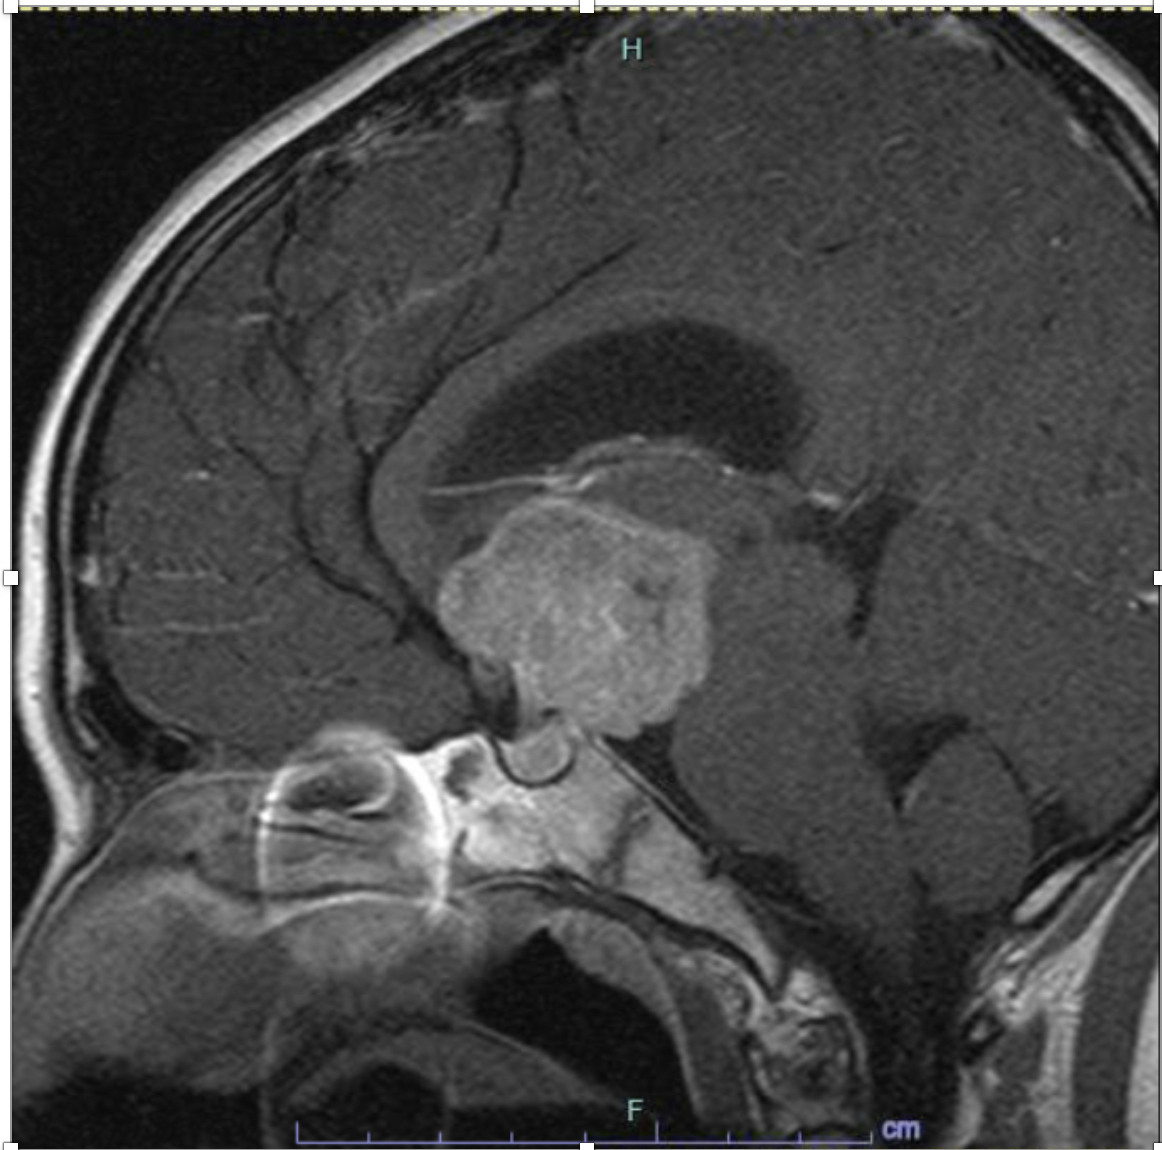

Case Presentation: 14-year-old female with history of depression, anxiety, and sexual abuse was referred to the adolescent clinic with 4 months of rapid weight loss, vomiting, and occasional headaches. Further history revealed several months of hiding and refusing food, although she denied body dysmorphia. Her exam revealed a pre-pubertal female with absent secondary sex characteristics, normal neurologic exam and positive orthostatic vitals. She was admitted for severe malnutrition secondary to possible anorexia nervosa and started on an eating disorder protocol. Lab work on admission was significant for undetectable LH, FSH, estradiol and TSH levels, normal T3 and T4, elevated ESR to 30 and negative celiac screen. During admission, she refused all oral nutrition and nasogastric feeds were initiated. She then developed polyuria, hypernatremia, hyperchloremia and hypoosmolar urine consistent with diabetes insipidus. Additional labs revealed a morning cortisol of 1ug/dL and prolactin of 103.2ng/mL. MRI of the brain revealed a large suprasellar mass with moderate hydrocephalus and significant compression of the pituitary gland. Her symptoms were suggestive of panhypopituitarism secondary to mass effect. Her symptoms improved with desmopressin and hydrocortisone replacement. She was then transferred to another center for neurosurgical evaluation and underwent transsphenoidal biopsy, which revealed a germinoma. Chemotherapy was started with plans for future radiation treatment.

Discussion: Germinomas are a form of intracranial germ cell tumor, which comprise 3-15% of primary pediatric intracranial neoplasms. Most cases are diagnosed in patients less than 20 years of age with peak incidence between 10-12 years old. Males are more commonly affected than females. Location vary by sex, with suprasellar location being more common in females, as in our patient, and pineal locations being more common in males. Diabetes insipidus is the most common endocrine manifestation and can precede radiologic diagnosis. Other endocrine abnormalities such as delayed or precocious puberty, growth retardation, and hypopituitarism can also be seen (1).